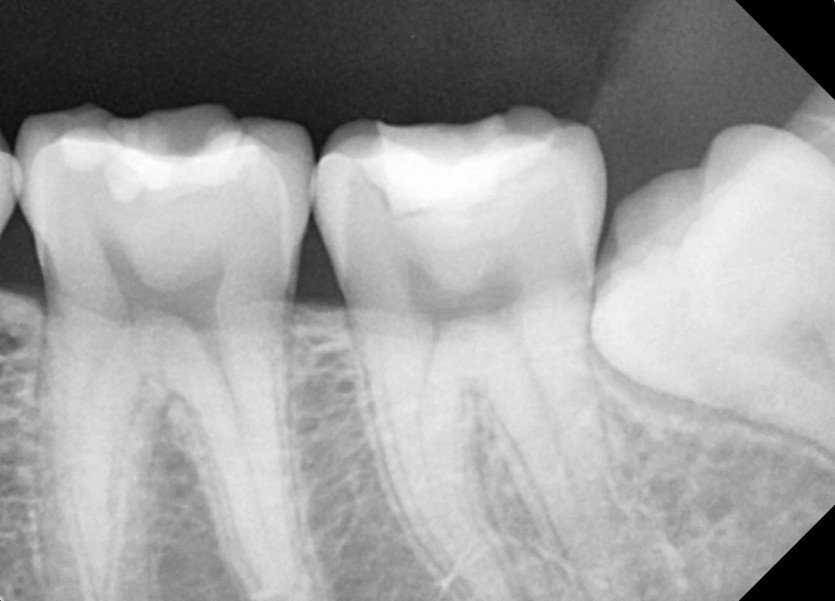

#28,38,48 사랑니 발치

구강 외과 전문의가 당일 발치했습니다.